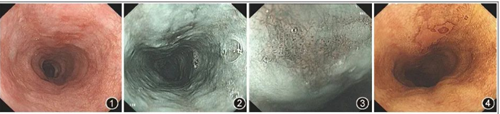

胃镜检查是发现早期食管癌的有效手段

对于胃镜筛查的推荐